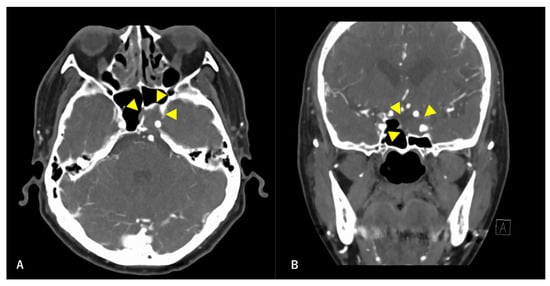

Figure 1. Preoperative contrast-enhanced computed tomography (CT) findings. Axial section (A) and coronal (B) images are shown. An isodense area with surrounding bone destruction is observed in the left sphenoid sinus, and no surrounding bone is observed around the internal carotid artery (ICA). Arrowheads indicate tumors.

A 60-year-old man without any symptoms presented to the otorhinolaryngology department with a suspected neoplastic lesion in the left sphenoid sinus, detected on magnetic resonance imaging performed during a physical examination. Imaging modalities showed that the tumor extended from the left sphenoid sinus to the area surrounding the ICA, with associated bone destruction, raising a suspicion of malignancy (Figure 1 and Figure 2). Neither regional lymph node nor distant metastases were observed. An otorhinolaryngologist performed a transnasal biopsy of the tumor under general anesthesia to determine the course of treatment. Immunohistochemical staining was positive for cluster of differentiation (CD) 56, synaptophysin, and chromogranin A. In contrast, cytokeratin AE1/AE3 staining was negative (Figure 3). Notably, there were few S-100 protein-positive cells, which are suggestive of the sustentacular cells typical of ONB. Because the diagnosis was difficult, the pathologists referred the specimens to a more specialized laboratory for additional testing. Further immunohistochemical tests were negative for both Nirenberg and Kim homeobox (NKX) 2.2 and CD99; therefore, the patient was diagnosed with olfactory neuroblastoma with Hymas pathological grade I and Kadish stage C.